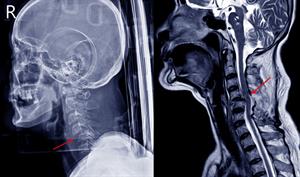

- Mugurkaula traumas. Ja cietušais ir bijis ceļu satiksmes negadījumā, kritis no liela augstuma, lēcis ūdenī, pieņem, ka cietušajam var būt traumēts mugurkauls.

Mugurkaula trauma